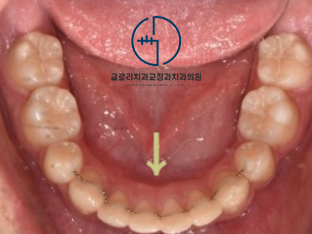

저작활동에 중요한 역할을 하는 어금니(# 17)가

아예 협측쪽으로 돌아가 있었습니다.

-> # 17 가위교합(sissors bite)

『자! 이제 엇갈려 물리던 17번이

어떻게 바뀌었는지 확인을 해봐야겠죠?』

제위치를 찾아서 올곧게 자리를 잡고 있는

두 번째 큰 어금니가 눈에 띕니다ㅎㅎ

고무줄의 탄성을 이용하여

밖으로 돌아가 있는 치아를

안쪽으로 유도했는데요.